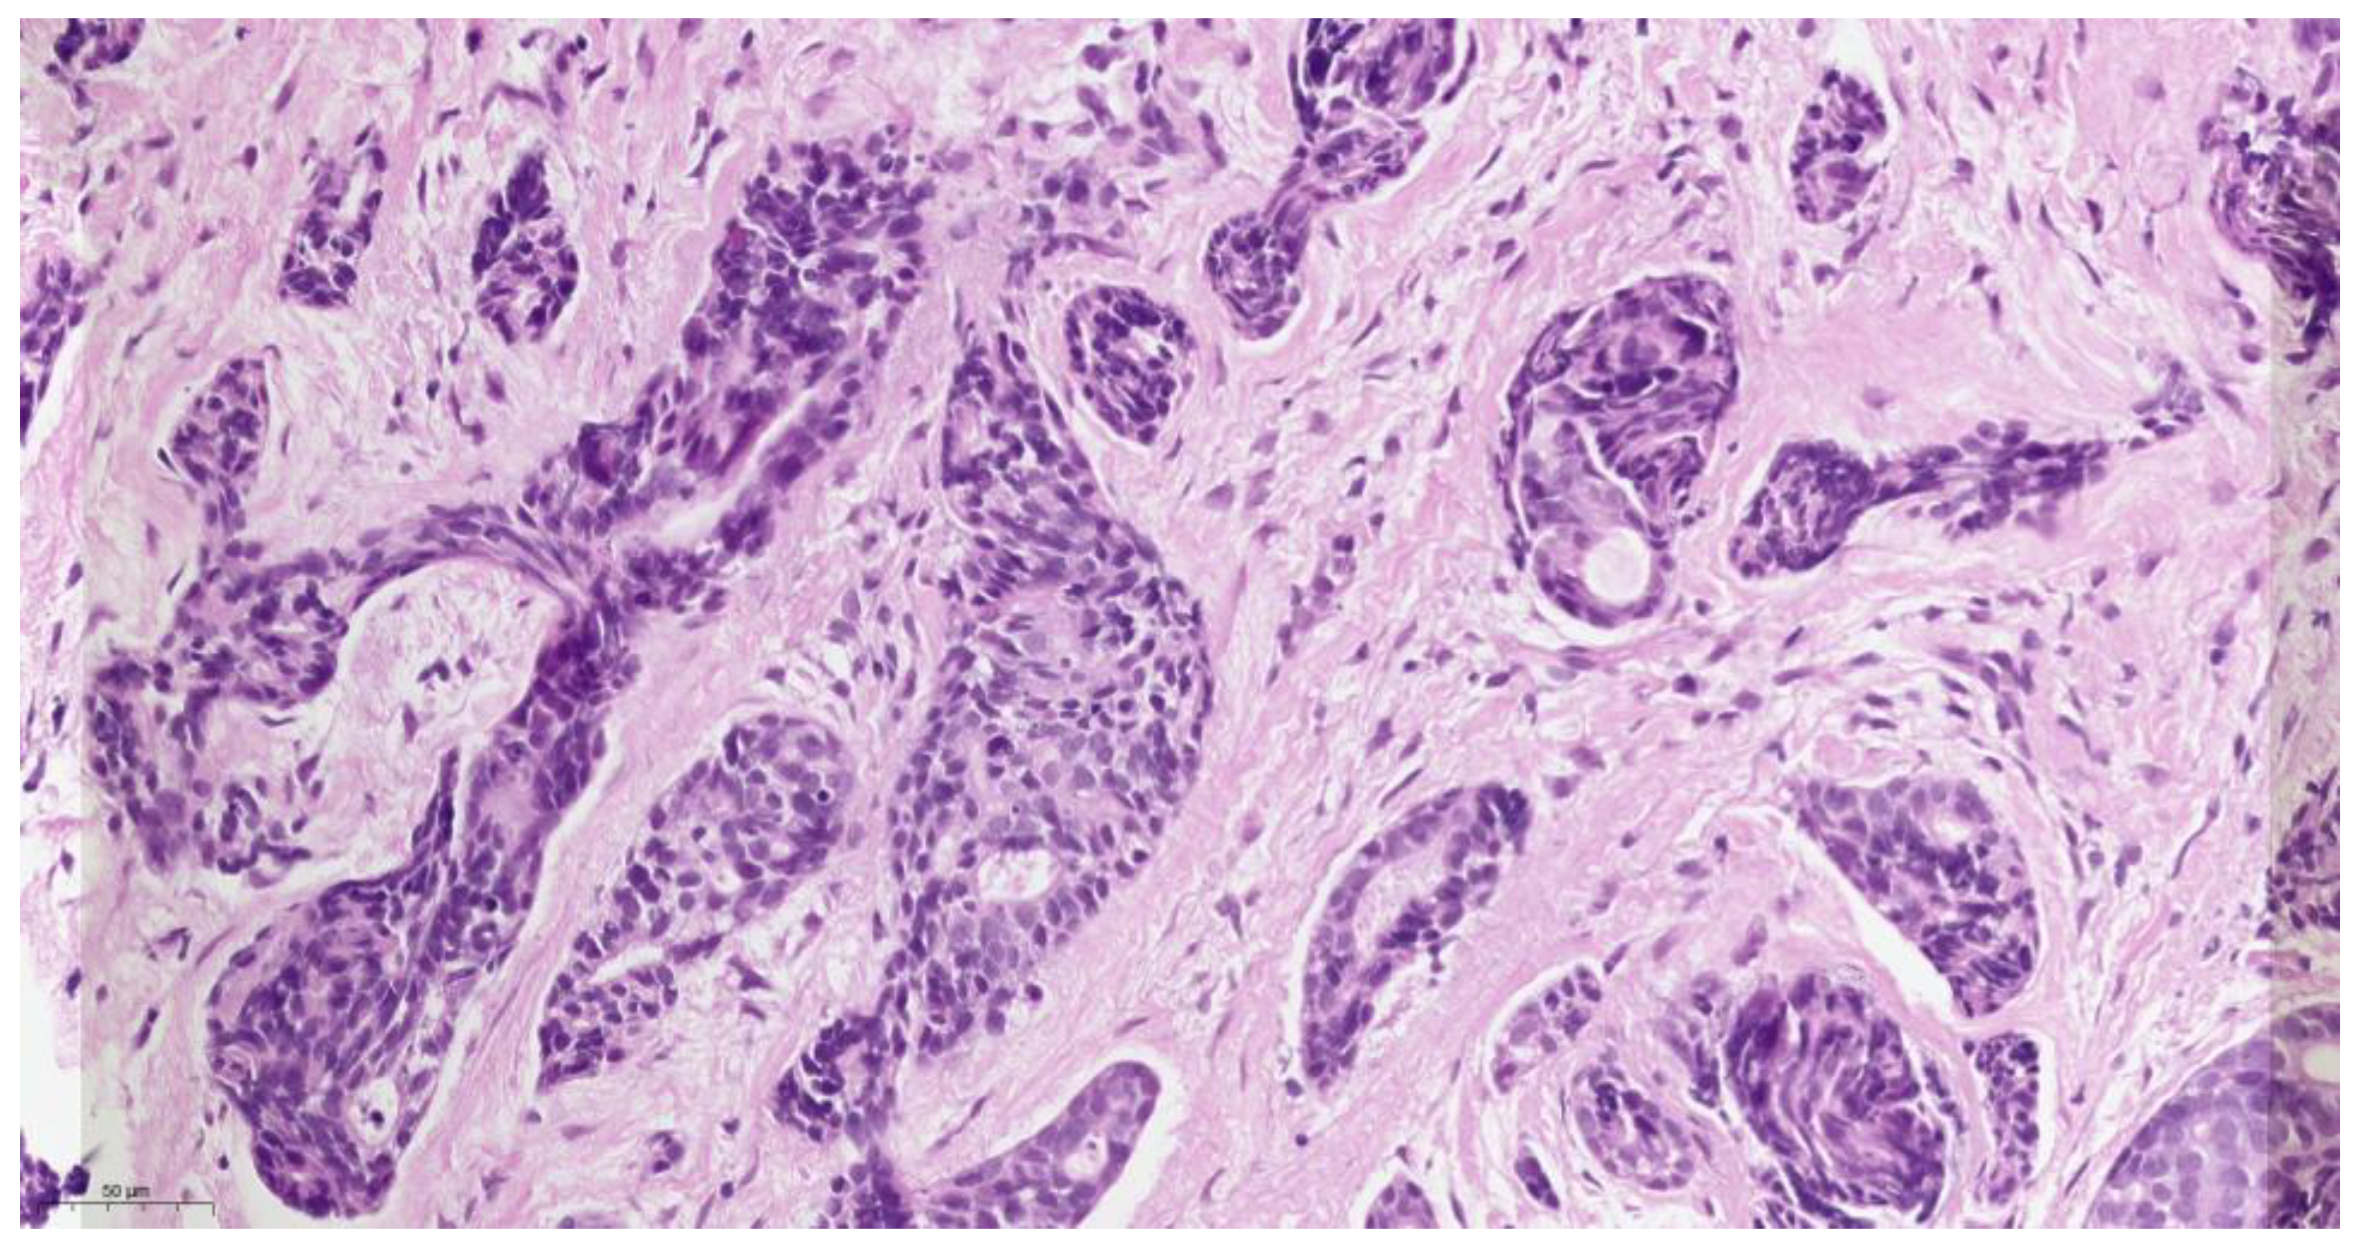

Histopathological examination (Figure 3) of the biopsied tissue indicated the diagnosis of cystic adenoid carcinoma, with the presence of glandular, cribriform, and predominantly solid growth patterns. The tumor is composed of small, rounded cells with a small amount of cytoplasm, basophilic staining, and a large, rounded nucleus with a small nucleus. The stroma of the tumor is desmoplastic, which means that there is an overgrowth of fibro-conjunctive tissue around the tumor.

The histopathology of ACC is characterized by a biphasic growth pattern, with a combination of solid, cribriform, and tubular structures. The tumor cells have a characteristic “Swiss cheese” appearance due to the presence of pseudocysts formed by tumor cells. The pseudocysts are lined by epithelial cells that secrete mucinous or hyaline material. The tumor cells are typically small and uniform in size, with scant cytoplasm and a round to oval nucleus. ACC has a tendency to invade surrounding tissues and can infiltrate nerves, blood vessels, and bone [13]. In our case, histopathological grading was predominantly solid. This indicates that the tumor had a solid growth pattern, with less evidence of the typical cribriform and tubular structures that are commonly seen in ACC. The solid growth pattern of ACC was associated with a more aggressive clinical course and a higher risk of metastasis.

Figure 3. Hematoxylin-eosin staining of ACC, original magnification ×400.